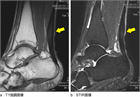

1. アキレス腱症とアキレス腱付着部症の病態をしっかり区別する必要がある(推奨度1)

1. 診断、治療、経過評価に、超音波画像検査が有用である(推奨度2